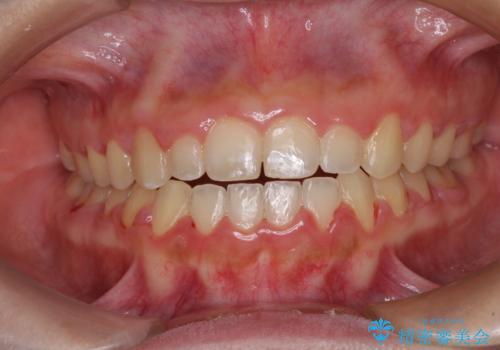

- 八重歯や前歯のデコボコを気にして来院された患者様です。

目立たない装置を希望されたので、上顎が裏側装置のハーフリンガルを選択し、上下左右の小臼歯(計4歯)を抜歯して矯正治療を行うこととしました。

補助装置を併用することで、八重歯を速やかに改善し、治療期間の短縮を図ることとしました。